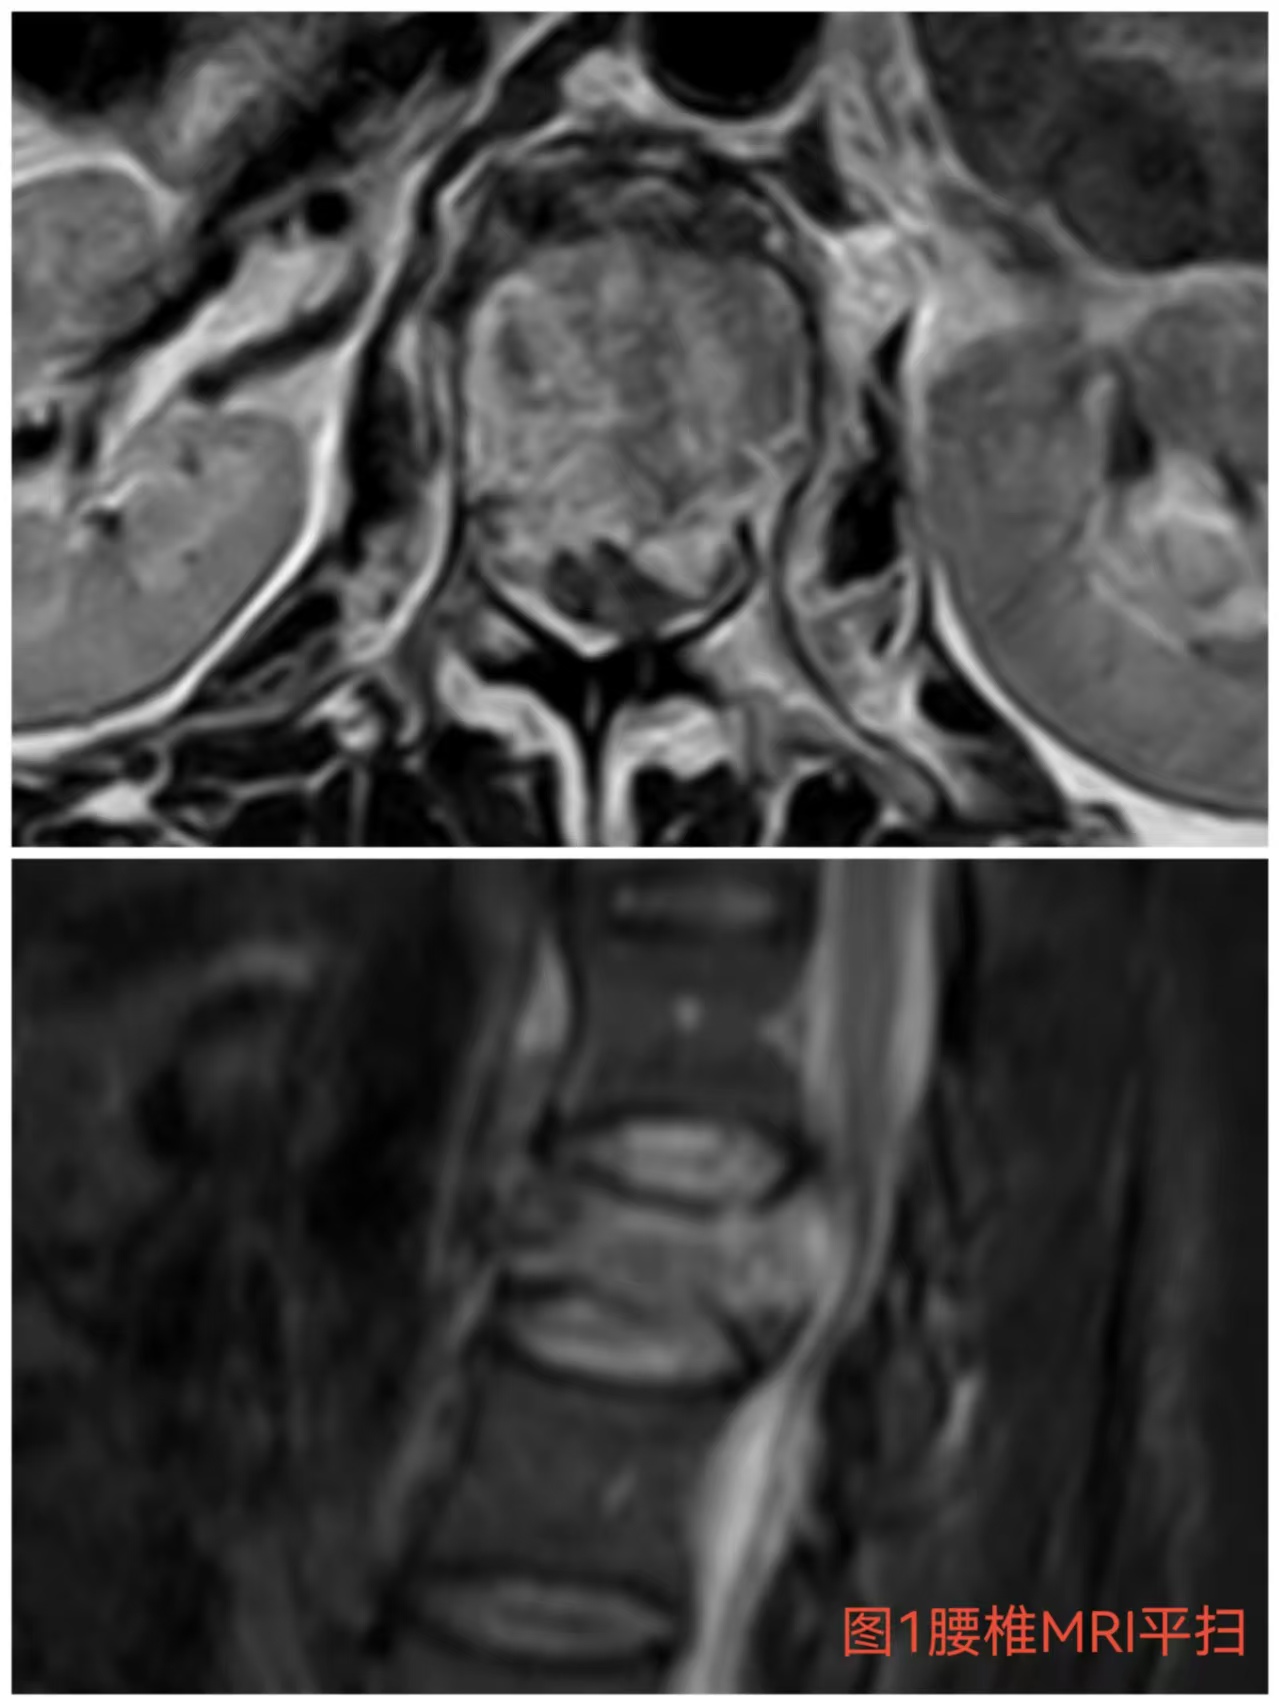

入院時(shí)患者躺在床上不能動(dòng)彈,眼神中透漏著(zhù)深深的無(wú)助,對于她來(lái)說(shuō)這種傷情無(wú)疑是沉重的,尤其是腹股溝以下感覺(jué)消失、雙下肢肌力0級,這意味著(zhù)其下肢無(wú)法活動(dòng)及站立,仿佛被命運按下了暫停鍵;與病人及家屬充分溝通病情后,第一時(shí)間給予對癥治療,監測患者生命體征,行腰椎核磁檢查(圖1)提示:腰1椎體爆裂性骨折,椎體后緣塌陷致骨性椎管狹窄,壓迫脊髓神經(jīng),結合患者病情及輔助檢查可診斷為:“L1椎體爆裂性骨折伴雙下肢截癱”。